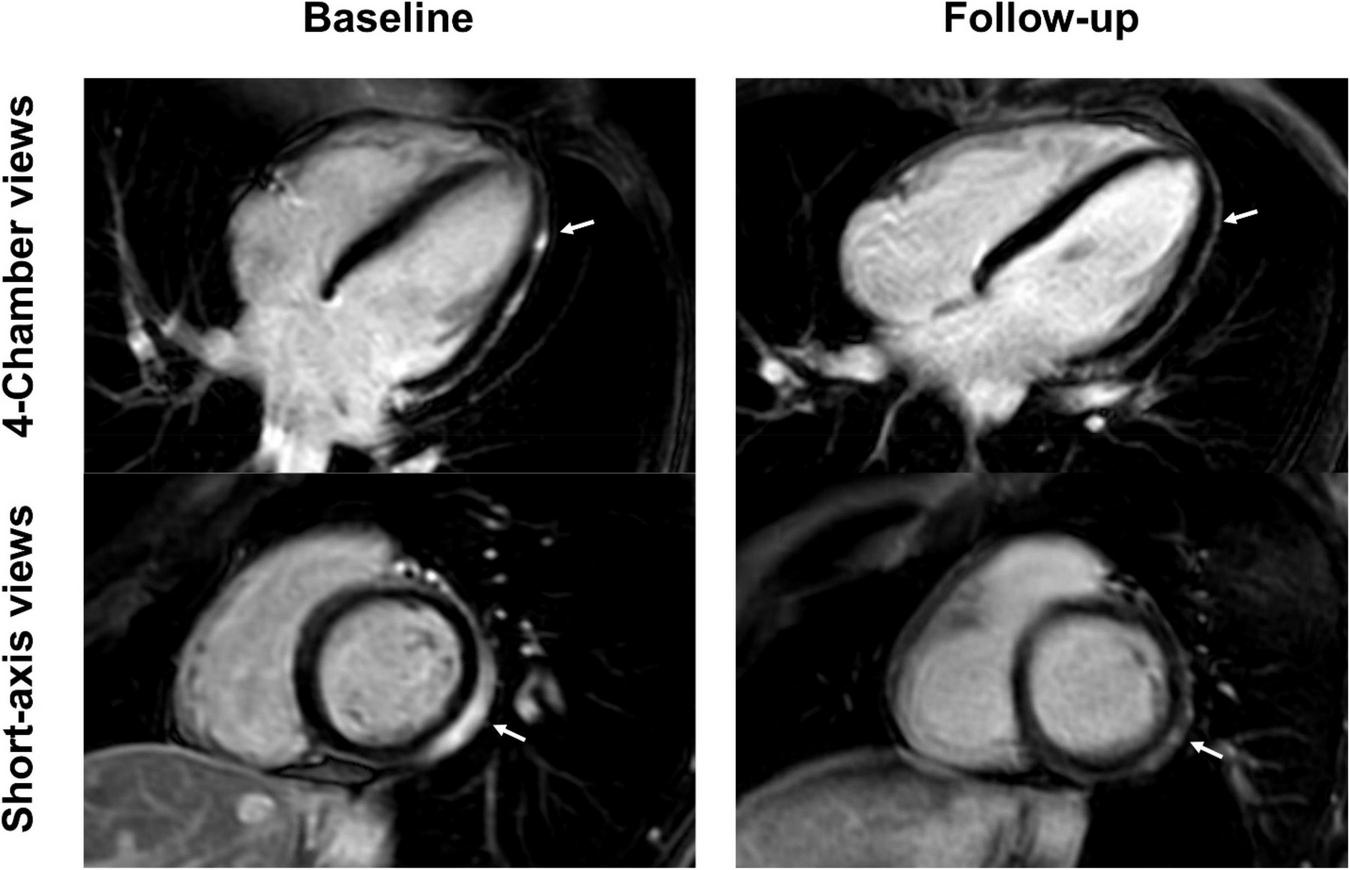

FIGURE 3

Short-axis and 4-chamber late gadolinium enhancement (LGE) views in a 28-year-old, previously healthy male after receiving his second Moderna vaccine. Reduction of subepicardial enhancement along the lateral wall from baseline (arrows) to follow-up 11-months later consistent with myocardial scarring. This patient reported new onset of occasional exertional dyspnea after initial acute vaccine associated myocarditis.